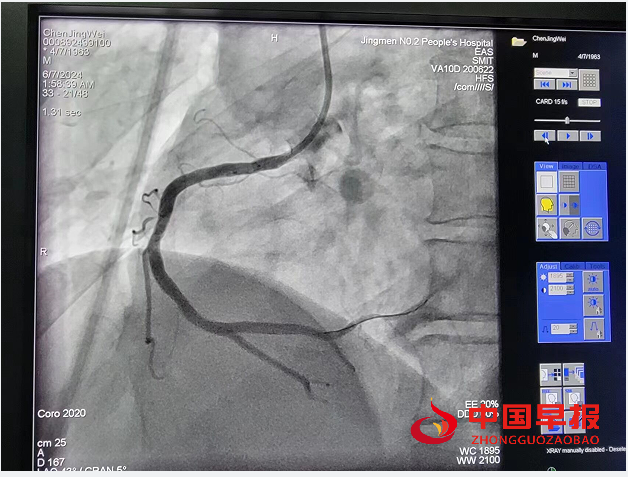

支架前后造影图

这也是沈集镇中心卫生院开展“323心脑血管一体化”防治和胸痛救治单元成立以来的第一起成功救治案例,也使该院实现了溶栓手术零的突破。时钟滴答,生命危在旦夕。与时间赛跑,就是在和死神搏斗。61岁男性患者感到恶心、呕吐、左侧手臂无力,阵发心慌、胸闷约1小时,立即到沈集镇中心卫生院就诊,医生初步判断为急性心肌梗死,立即开通胸痛急救绿色通道,启动救治流程;22:39上传心电图至胸痛救治网络微信群,电话会诊上级胸痛中心专家,确诊为“急性下壁心肌梗死”,急查心肌肌钙蛋白cTnI0<0.03ng/ml;22:45给予患者“心梗一包药”,建立静脉通道、吸氧、心电监护,23时13分静脉注射肝素4000u,瑞替普酶18毫克,20分钟后复查心电图提示ST段较前稍回落,患者胸痛症状稍缓解;23时54分转运至荆门市人民医院胸痛中心,立即行急诊PCI,证实为右冠状动脉中段重度狭窄,术中放置支架血管再通,成功救治了一名濒临死亡患者。